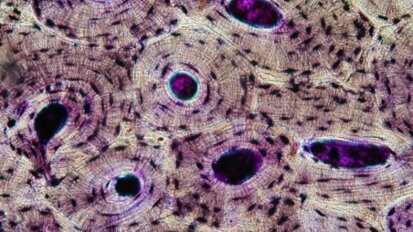

Nowe możliwości w leczeniu nowotworów

Nowotwory jamy ustnej stanowią poważny odsetek wszystkich zachorowań na raka. Nowa terapia genowa może dać nadzieję na zwiększenie powodzenia ...